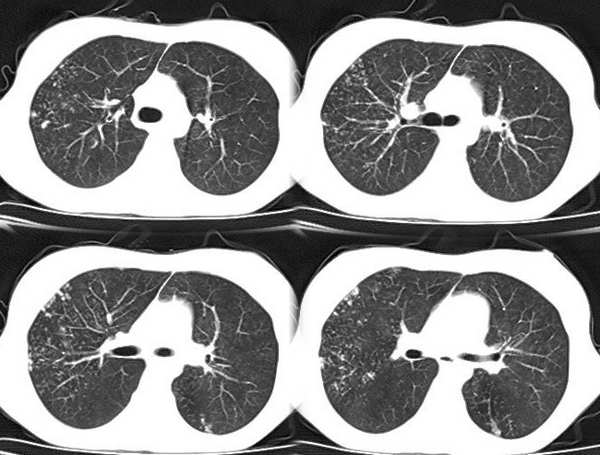

以下是引用x线在2006-2-2 17:37:00的发言:[br]结合病史支持“ct拟诊:双侧tb,左下叶结核球,左下叶局限性轻度支扩。”双下叶及左舌叶淡薄的毛玻璃密度影,我考虑为炎性渗出。另:是否合并霉菌感染须进一步检查确定。